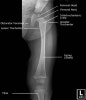

- 3 Lines

- Acetabular angle

The acetabular angle using Hilgenreiner's line should be less than 28 degrees at birth.

The angle should become progressively shallower with age.

The normal range is 33 to 38 degrees.

Angles above 47 degrees are seen in patients with acetabular dysplasia.

A measurement between 39 and 46 degrees is indeterminate.

5. Hip Frog legs view

- Femur AP view

- Femur Lateral view